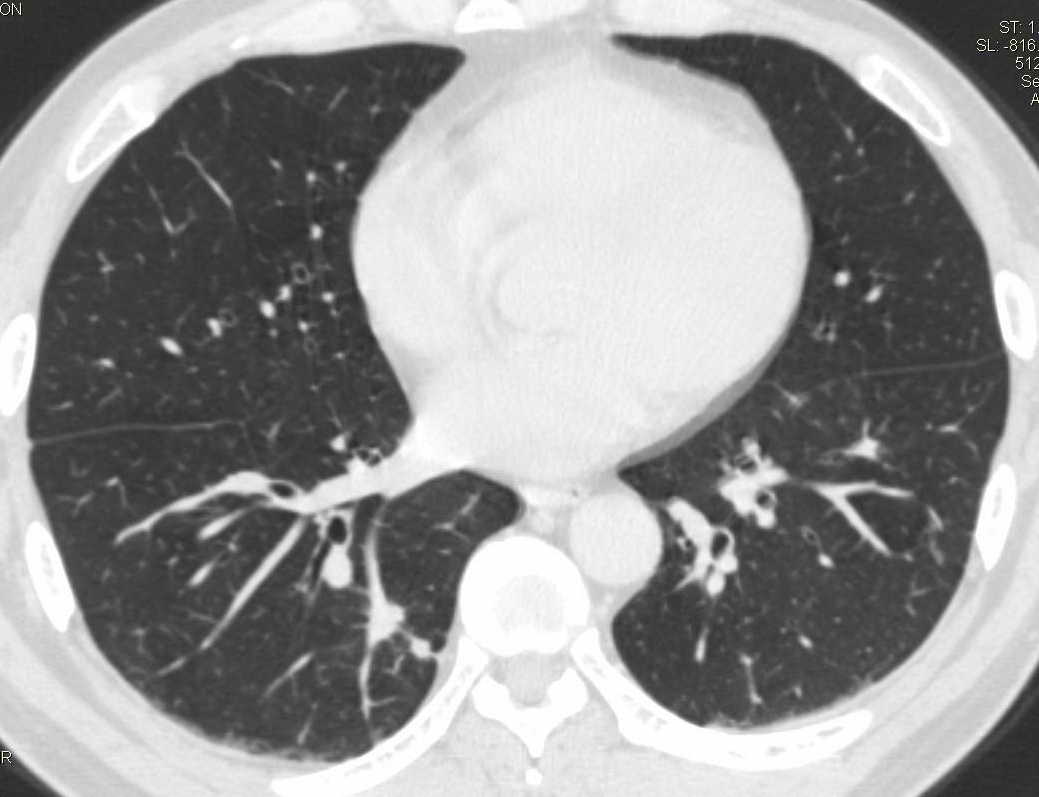

标题: CT15857:男性 58岁 咳痰带血 无发热 请各位大侠发表一下意见 [打印本页]

标题: CT15857:男性 58岁 咳痰带血 无发热 请各位大侠发表一下意见

两肺下叶肺纹理增多、增粗并呈“树芽状”改变。支气管扩张呈囊状,部分呈柱状改变。其周围可见散在的斑片样及条索样密度增高影,右肺下叶近叶间胸膜可见一形态不规则的高密度结节影,并与胸膜粘连。

考虑:支扩并发感染。

双肺多发炎性病灶,结核可能性大,建议抗炎治疗复查.右肺下叶前基底段结节灶,高度警惕肺癌可能

双肺间质性改变(间质纤维化?)伴支扩。右肺下叶有毛刺的小结节,考虑周围型肺癌可能性。